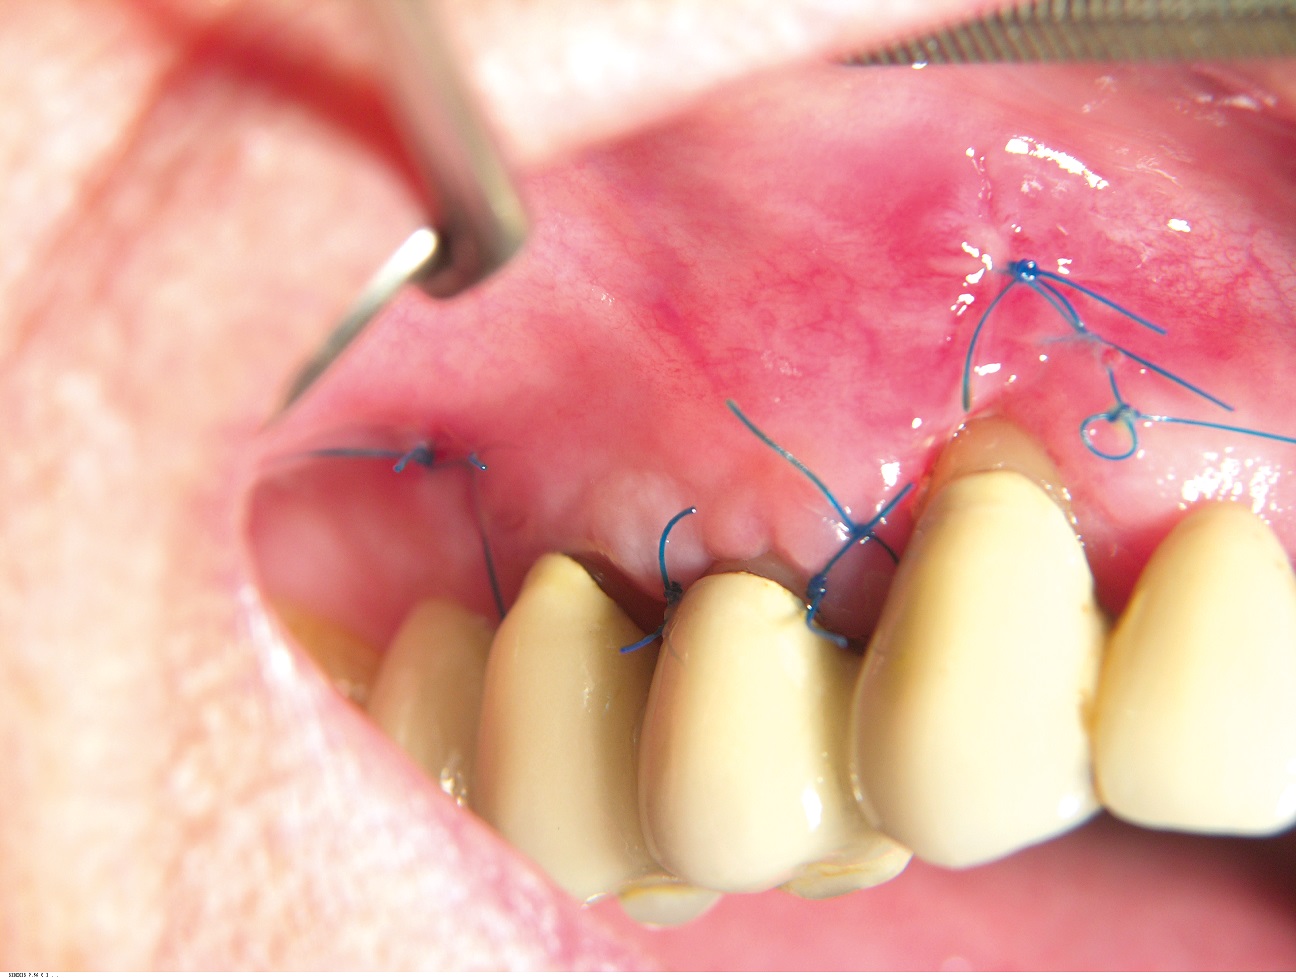

08/10 - Situation at the time of suture removal.GTR for the treatment of a deep three-dimensional intrabony defect using cerabone®, collprotect® membrane and Straumann® Emdogain® - Dr. T. Schwaar